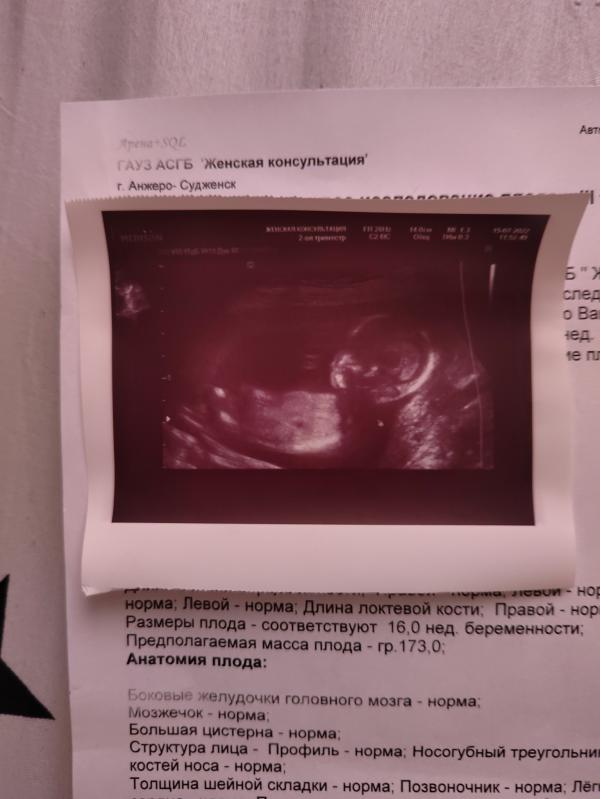

Это первое фото моего 4-го мальчика ! Я счастлива , малыш здоров , сосет пальчик. Показал пол не сразу, долго сопротивлялся , потом повернулся передом раздвинул ножки , а от туда разумеентся вывалилось мужское достоинство !))) Девочки посоветуйте красивые имена для мальчиков, а то по-моему у меня фантазия закончилась !